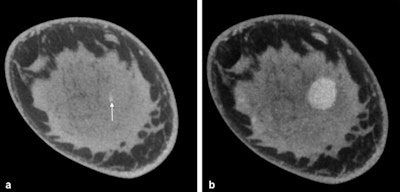

At DRK 2016, she is reporting on a further development in tomosynthesis: cone-beam breast CT. Unlike tomosynthesis, this method actually allows for a 3D dataset to be acquired.

Cone-beam breast CT has some advantages that may render the method an interesting option for breast cancer screening in the future. On the one hand, thanks to 3D image acquisition, the location of suspicious structures can be determined precisely in all spatial directions. On the other hand, findings can be evaluated immediately by taking a tissue sample, thus sparing the affected women days of uncertainty. Compared with mammography, the method is also more comfortable for the women because the breast does not need to be compressed during the examination.

However, even this method is somewhat dependent on the density of the breast: The detection rates are lower with dense breast tissue. In this case, the detection rate can be improved by administering a contrast agent. To evaluate how cone-beam CT fares against mammography, the researchers are now embarking on a larger clinical study, during which the team from Göttingen will collaborate with their peers in Norway and Berlin.